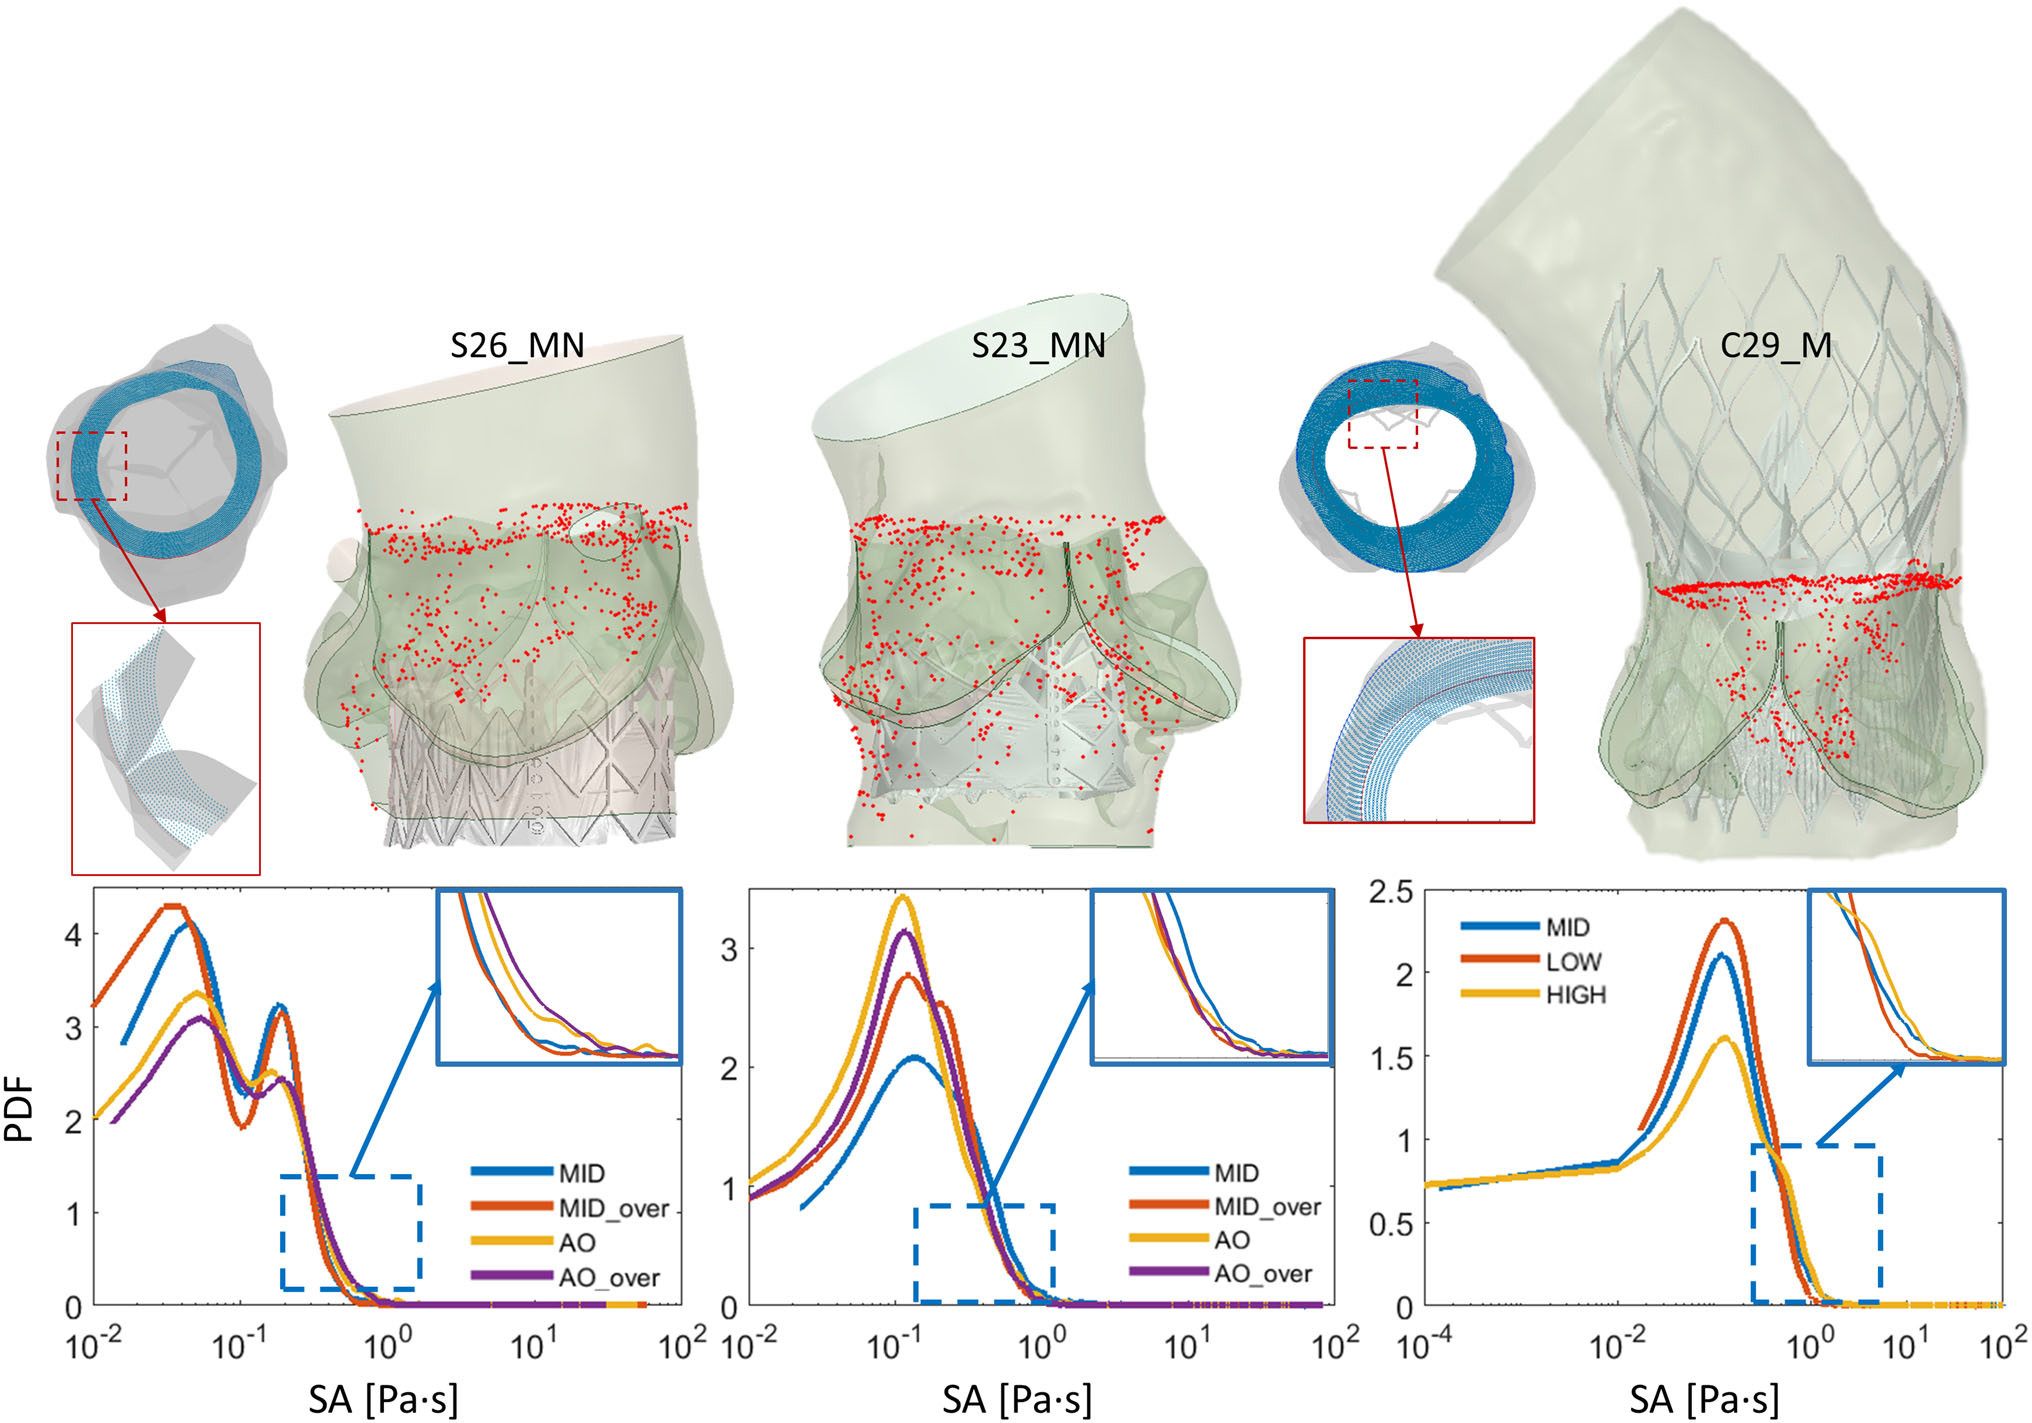

- Probability density functions (PDFs) of the accumulated stresses for the flowing platelets were computed for each device (which represents the “thrombogenic footprint” for each respective device), analyze thrombogenic potential of different leaflet designs by comparing PDFs

- Here, we see the top 100 stress accumulation platelet trajectories colored by stress. In particular, we see the highest stresses near the surfaces of the prosthetic leaflets and at the leaflet tips, demonstrating the key idea that platelets interact differently with varying valve designs and experience different magnitudes of stress during their trajectories as they flow past each prosthetic device

- Hemodynamics and leaflet kinematics were different for each TAVR design, where designs #1-2 and the SAPIEN3 showed lower peak fluid velocities as compared to the other devices, likely due to these leaflets producing larger orifice areas and having reduced leaflet fluttering, which may be due to more optimal surface area and leaflet inflation

- The conversion of the data into PDFs also support this when looking at the tail region of the curves, as this region highlights the stress magnitudes that are likely to cause platelet activation. The original stress accumulation data was normalized to time in order to consider the small number of cardiac cycles simulated here. When doing this, the data distribution becomes unbiased and agrees well with the previous flow results since the commercial Evolut R, along with parametric designs #3-5 show the highest thrombogenic risk from the larger PDF tails

TAVR in BAV Patients - Thrombogenic Risk Analysis

- We analyzed thrombogenic risk of this device and compared results to commercial devices currently used to treat BAV patients. Specifically, we modeled the 29-mm Evolut R (EV29) TAVR deployment first with the commercial leaflets in place, and then by replacing the commercial leaflets with our PolyV-B design, all in patient-specific models

- The novel design resulted in larger orifice areas and reduced jet velocities, outperforming the commercial Evolut R. The thrombogenicity comparison shows that the PolyV-B design has a smaller thrombogenic footprint when compared to the Evolut R

- In each panel, we see the red curve representing the commercial device was shifted towards higher stress accumulation values in addition to having more pronounced tail regions, increasing the likelihood of activating platelets. This is also indicated in the tabulated data, where the median stress accumulation among the highest or top 100 trajectories was largest for the Evolut R, indicating increased thrombogenic risk